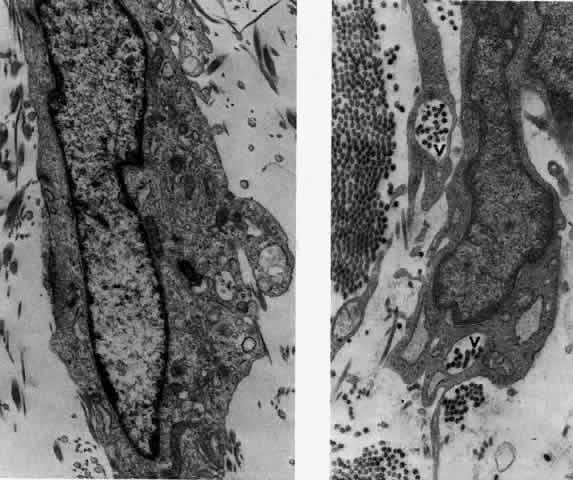

What is clinically represented solely by inflammation and edema is histopathologically a granulomatous lesion of the sclera, the center of which consists largely of plasma cells, lymphocytes, and mast cells (Figs. 21 through 23). Foster and colleagues have identified the cellular subsets and glycoproteins in both necrotizing and non-necrotizing scleritis.22 This shows an active T-cell inflammatory response with a high CD4/CD8 ratio and increased HLA/DR and CD14, indicating a macrophage-induced response that would lead to granuloma formation. Remote from the granuloma, the fibrocytes of the sclera become activated, the proteoglycan adjacent to them becomes altered, and the collagen fibrils of the sclera become unraveled (Figs. 23 and 24). These changes appear to take place prior to the invasion of the stroma by cells of the granuloma.20 The vessels in and around the necrotic area show medial necrosis and perivascular cuffing with lymphocytes, and endothelial swelling with microvascular occlusion. Ninety-six percent of the specimens examined by Foster and associates show a microangiopathy characterized by a neutrophil infiltrate in and around the vessel wall.22–23 This is most obvious at the center of the lesion where there may be occlusion of the vessel, thrombosis, or even aneurysm formation (Fig. 25). From these pathologic investigations, clinical observations, animal experiments, and the results of fluorescein angiography, it would appear that the scleral inflammation is initiated either by trauma (be it accidental or surgical)23–25 or by bacterial or viral infection. If circulating immune complexes are present because of the poor blood flow, they become precipitated in and around the vessel walls in the area of inflammation. In other patients, a persistence of tissue damage will lead to autoimmunization. Damage to the endothelial cells of the microvasculature leads to changes within the vessels detectable on angiography and to catabolic changes in the surrounding tissues. These changes, in turn, allow the granulomatous response that is seen in histopathologic sections, the first detectable change being in the scleral fibrocytes and the proteoglycan and collagen remote from the site of cellular infiltration.